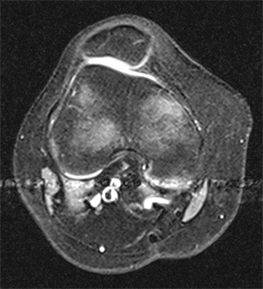

The patella dislocation was on the left side in 12 (46.15%) cases and the right side in 14 (53.85%). The dominant side was involved in 16 (61.53%) cases. The dislocation occurred through trauma in 15 (57.69%) cases, whilst going up and down stairs in 4 (15.39%) cases, while doing sports in 4 (15.39%) cases, while playing a game in 2 (7.69%) cases and while turning over in sleep in 1 (3.84%) case. Complaints related to the patellofemoral joint before the dislocaton developed were stated by 7 (26.92%) of those whose dislocation was the result of trauma, by 4 (15.39%) of those going up and down stairs, by 2 (7.69%) of those doing sports, by 1 (3.84%, case No 26) playing a game and by the 1 case (3.84%, case No 16) while turning over in sleep. Reduction was made immediately by the patient themself or by a relative at the scene of the incident in 16 (61.53%) cases, in the Emergency Department in 8 (30.76%) cases and by a doctor or auxiliary healthcare personnel in the ambulance in 2 (7.69%) cases (Table 1) (Figure 1(a) and Figure 1(b)).

Figure 1. (a) MRI image taken in the Emergency Department of a case on presentation with acute patella dislocation. (b) MRI image taken in the Emergency Department of a case with acute patella dislocation after reduction.